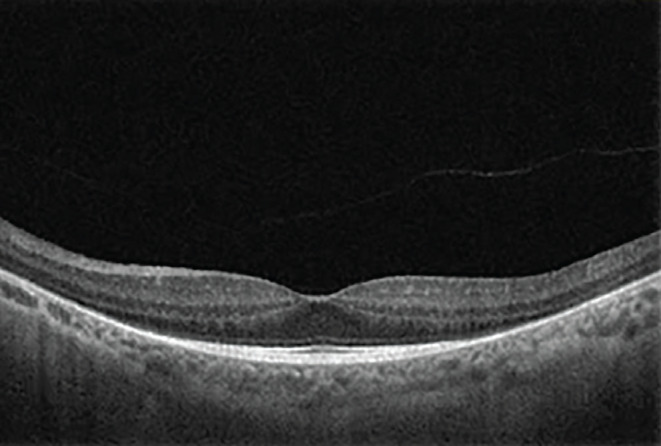

Jeune syndrome (JS), first described by Jeune as asphyxiating thoracic dystrophy, is an autosomal recessive osteochondrodysplasia with characteristic skeletal abnormalities and variable renal, hepatic, pancreatic, and ocular complications. Approximately 1 in every 100,000 to 130,000 babies is born with JS. Most patients with JS have respiratory distress due to inadequate lung development and many lose their lives due to respiratory failure. Those who survive have serious comorbidities. In terms of ophthalmological diseases, JS is classified among the hereditary syndromic retinopathies. Most, if not all, hereditary syndromic retinopathies can be analyzed in two main groups: inherited metabolic diseases and ciliopathies. The main cause of ocular pathologies in JS is genetic mutations in ciliary proteins that prevent normal function of retinal photoreceptor cells. Here we describe a patient with JS who presented with the complaint of night blindness. Although Snellen visual acuity was 20/20, the patient’s visual function was severely impaired due to photoreceptor dysfunction caused by ciliopathy secondary to the genetic mutation. This case shows that in patients with syndromic comorbidities accompanying nyctalopia, even those with perfect visual acuity, hereditary retinal dystrophies should be considered and asphyxiating thoracic dystrophy (JS) included in the differential diagnosis. Multimodal retinal imaging, including structural and functional assessments, should be used for the diagnosis and genetic counselling should also be provided.

Abstract Image